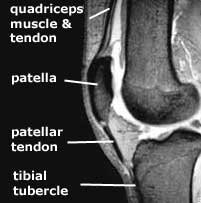

The term 'extensor mechanism' implies the unbroken chain of anatomical structures which cause the leg to extend -

The whole of this chain can be affected by the arthrofibrosis process.

The next thing that produces a loss of flexion that is very difficult to deal with is shortening of the quadriceps muscle. We documented in our studies that the quadriceps mechanism and the muscle actually shorten because scar tissue prohibits normal muscle contractions and lengthening. This muscle may start to shorten as early as four months following an injury or operation. And before that, the patellar tendon also will begin shorten, resulting in what is termed a patella infera condition.

Once the quadriceps muscle/patellar tendon mechanism goes through this shortening process, it is extremely difficult to recover the normal length. Once the surgeon has released all the tissues that I just mentioned above, the final thing that may still be limiting flexion is shortening in the quadriceps muscle and patellar tendon.

It is very difficult to measure how much shortening has occurred in the quadriceps tendon. The surgeon can get an idea if he or she can only flex the knee ninety to a hundred degrees for example. However, one can measure the amount of patellar tendon shortening using a method we published many years ago. A lateral x-ray is obtained of both knees and the height of the patella is measured, which allows interpretation of the length of the patellar tendon. The measurement of the involved knee is compared with the opposite knee, and the resulting difference indicates the amount of patella infera present.

The second factor which may limit patellar tendon medial and lateral glide is adhesion of the patellar tendon to the tibia. The normal space is lost, requiring the surgeon to free up the patellar tendon. Otherwise, it will stick down to the tibia at the top of the joint rather than its normal postion at the tibial tubercle.